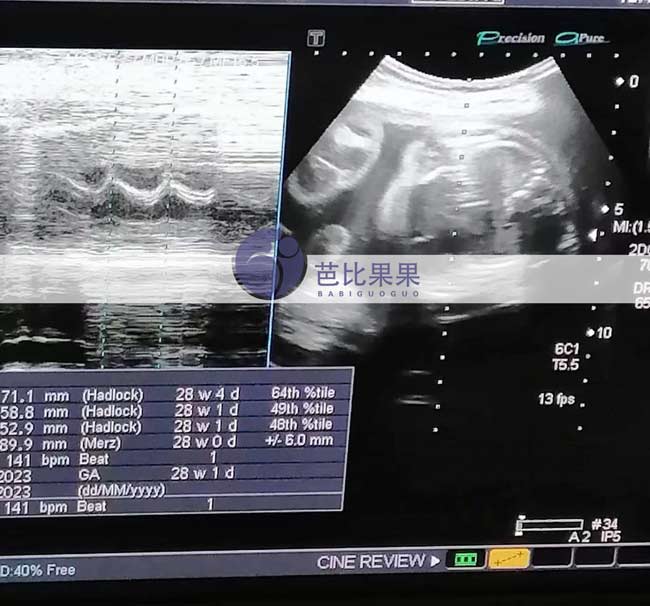

昆明Z女士家的乌克兰试管妈妈按时来医院28周的B超孕检

昆明Z女士家的乌克兰试管妈妈按时来医院做了28周的B超孕检,得知胎儿发育得很好,妈妈露出开心的笑容